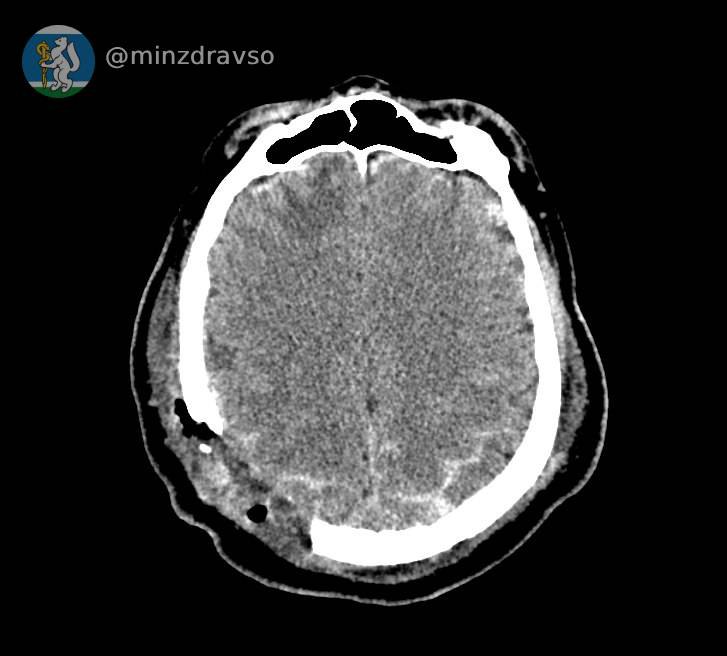

В Свердловской области благодаря усилиям врачей из Серова, Нижнего Тагила и Екатеринбурга удалось спасти 57-летнего мужчину, пострадавшего от удара по голове стрелой строительного крана.

Как рассказали на информационном портале регионального Минздрава «Здоровье уральцев», у мужчины была тяжелейшая черепно-мозговая травма. Любой из осколков черепа, повредивших мозг, мог стать причиной смерти.

Провести компьютерную томографию, чтобы понять, как именно раскололся череп, и стабилизировать состояние пациента оперативно смогли врачи Серова. Затем, после консультации с профильными специалистами из Екатеринбурга, мужчину экстренно перевезли в больницу Нижнего Тагила, где его уже ждала операционная бригада: врачи удалили осколки костей и восстановили целостность твёрдой мозговой оболочки.

Фото: Свердловский Минздрав